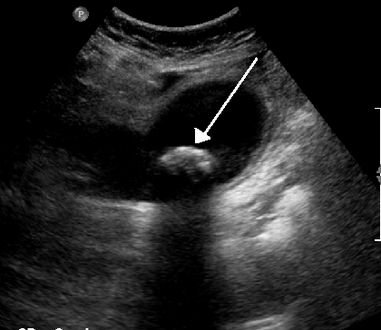

On abdominal ultrasound, sinking gallstones usually have posterior acoustic shadowing. In floating gallstones, reverberation echoes (or comet-tail artifact) is seen instead in a clinical condition called adenomyomatosis. Another sign is wall-echo-shadow (WES) triad (or double-arc shadow) which is also characteristic of gallstones.[38]

A 1.9 cm gallstone impacted in the neck of the gallbladder and leading to cholecystitis as seen on ultrasound. There is 4 mm gall bladder wall thickening.

Biliary sludge and gallstones. There is borderline thickening of the gallbladder wall.